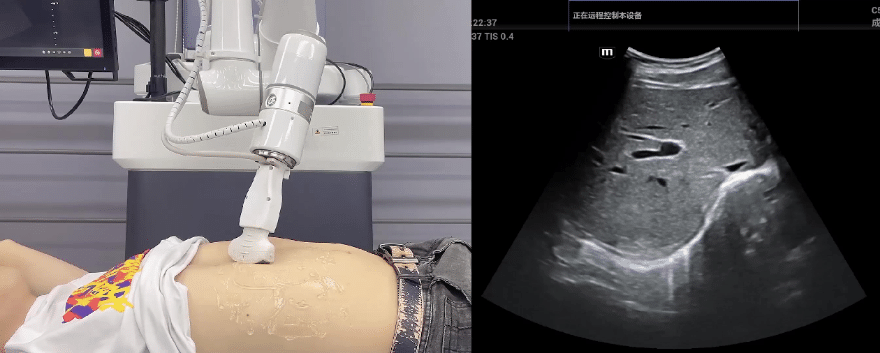

金年會(huì)jinnian(金字招牌)誠信至上協(xié)作機(jī)器人搭載庫柏特自主研發(fā)的機(jī)器人遙操作、多模態(tài)數(shù)據(jù)采集與處理、機(jī)器人模仿學(xué)習(xí)、機(jī)器人力位控制等技術(shù)升級(jí)變革傳統(tǒng)超聲,可實(shí)現(xiàn)遠(yuǎn)程+自主超聲掃查與診斷,從傳統(tǒng)遠(yuǎn)程超聲僅能對(duì)話會(huì)診變革升級(jí)為能對(duì)話、能操作,使得基層患者可就近享受異地三甲專家掃診服務(wù)。實(shí)現(xiàn)專家端與患者端遠(yuǎn)程連接,并支持專家端與多路患者端自由切換控制。

金年會(huì)jinnian(金字招牌)誠信至上機(jī)器人末端搭載超生L13-3N線陣探頭,可以對(duì)淺表小器官和外周血管進(jìn)行超聲檢查;搭建C5-1s凸陣探頭,可以對(duì)腹部(肝、膽、胰、腎等器官進(jìn)行超聲檢查)

EC66協(xié)作機(jī)器人末端可搭載主流品牌高品質(zhì)超聲儀,讓操作指令和影像低延遲、高精準(zhǔn)、高保真?zhèn)鬏敚_保檢查可靠、醫(yī)患放心;智能力控等三重防護(hù)系統(tǒng),確保患者舒適、安全。

金年會(huì)jinnian(金字招牌)誠信至上協(xié)作機(jī)器人與超聲深度打通,最大程度保留醫(yī)生左右手同時(shí)操作傳統(tǒng)超聲的習(xí)慣,并改善其舒適性,超聲檢查實(shí)際應(yīng)用場(chǎng)景展示如下:

肝臟、膽囊、胰腺掃查